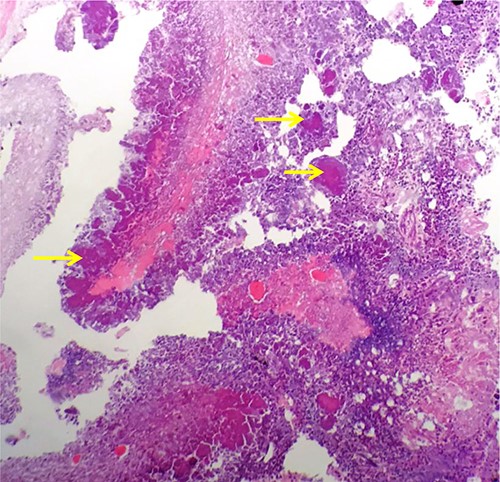

Macroscopic examination demonstrated extensive replacement of renal parenchyma with fatty and cystic purulent material. Numerous necrotic appearing nodules were seen (Fig. 1). Histology revealed multiple cavitating abscesses, chronic inflammation and sclerotic tissue. The macroscopically identified nodules histologically comprised of rod-shaped branching organisms, typical of Actinomyces species, with adjacent pink–purple granules consistent with sulphur granules (Fig. 2). The nature of these organisms were confirmed with Grocott methanimine silver and Gram stains. Microbiology testing was not performed as the sample had been placed in formalin. Post-operatively antibiotics were stopped and she was discharged home after 4 days.

Haematoxylin and Eosin stained formalin-fixed paraffin embedded kidney showing rod-shaped branching microorganisms typical of Actinomyces, with adjacent purple–pink granules consistent with sulphur granules (arrows).